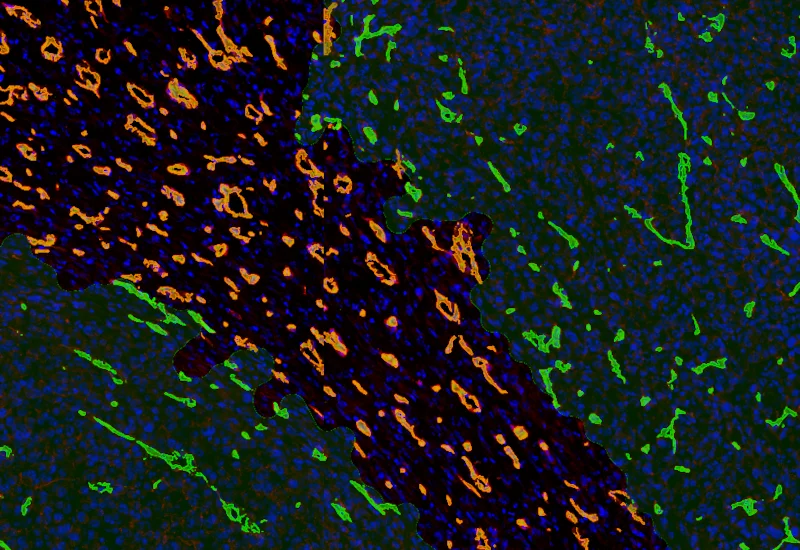

IF Immune status in situ

Characterize immune cell phenotypes relative to detected metastructures (e.g. tumors, glands), define distance ranges, measure cell-to-boundary distances inside/outside, and export up to 20 intensity, statistic, and morphometric parameters per cell compartment.

colon cancer, cytotoxic t cells, tumor microenvironment, PD1, CD8, spatial analysis, fluorescence

IF Tumor Vascularization

Segment tissue into tumor and stroma/healthy areas, detect CD31+ vessels, and quantify vessel number, area, density, and connectivity with configurable wall closing and distance linking.

vasculatization, cancer, stroma, tumor, blood vessels, CD31, spatial analysis, tumor microenvironment